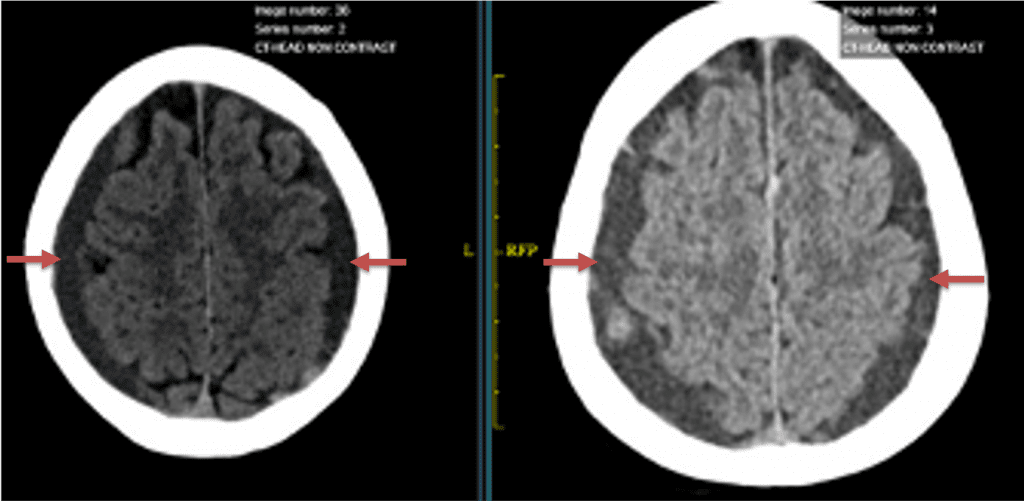

A woman in her 80s developed mild dizziness and headache following incidental trauma working in her garage one day. She presented several weeks later to the ER and was diagnosed with bilateral subdural hematomas, which were initially managed with observation, low dose Decadron, considering the mildness of symptoms, advanced age, and history of CLL with thrombocyptopenia (<100k). Over the next 4 weeks, the collections remained relatively stable with evidence of slight growth (10 to 12 mm thickness, and 2 mm right to left shift) on NCT (Figure 1. A and B).

Figure 1. A) 6 weeks post mild trauma B) 4 weeks post mild trauma demonstrates stable subacute subdural collections with mild growth and sulcal effacement.

CT follow-up at 1 week demonstrates early resorption. 2 weeks post MMA embolization, resolution of the left subdural collection with new small thin acute hemorrhage in an otherwise stable right subdural collection is observed (Figure 3. A and B).

Figure 3. A) 1 week post MMA embolization demonstrating decreasing thickness bilaterally B) 2 weeks post MMA demonstrates resolution on left, with small new acute component on right with overall decreased thickness.

Clinically, the patient improved over the few weeks with the occasional transient twinge of a headache, but resolution of dizziness. Follow-up CT at 10 weeks demonstrated complete resolution of the bilateral subdural hematomas with our patient completely asymptomatic and back to all of her activities of daily living. Considering her history of thrombocytopenia and CLL, we will continue to monitor her into the future and are excited about her progress and recovery. (Figure 4. A and B)

Figure 4. A and B) – 10 weeks following embolization demonstrates complete resolution of bilateral collections both acute and chronic.